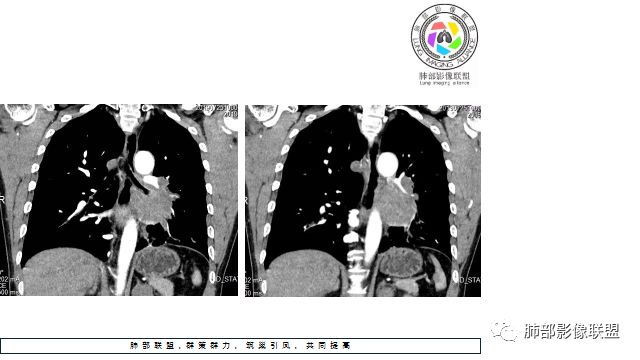

1.左下肺门区巨大肿块,支气管显示不清,轻度阻塞性炎症,没有明显肺不张,提示管腔受压狭窄可能性大于堵塞,这较少见于鳞癌。

2.病灶边缘光滑,未见明显分叶、毛刺,未见明显强化,这符合腺癌影像学特点,却符合神经内分泌癌表现。

3.病灶内密度均匀,轻到中度均匀强化,大病灶未见明显液化坏死区及空洞,不符合鳞癌而符合小细胞肺癌特点。

4.病灶内有肺动脉走形,血管局部受压,未见破坏,病灶乏血供,呈血管包埋或血管造影征;侵袭性力强及破坏力弱、血管漂浮都符合SCLC,所以鳞癌的可能性也不大。

5.左肺门块影或淋巴结肿大,竭力挤兑肺门血管结构,呈冰冻肺门;有时候SCLC可以单独呈现冰冻肺门,而没有没有冰冻纵隔。

7.须特别注意的是,肺门区的融合块影,不排除它可能仅仅为转移淋巴结。